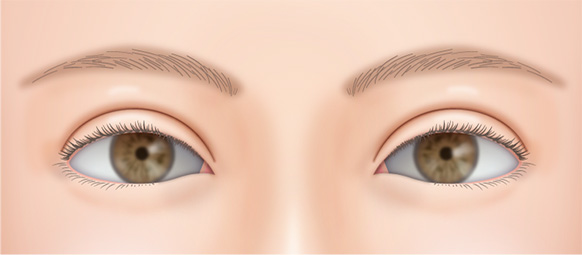

二重の幅が広くなり過ぎて、いかにも整形っぽい目になることがあります。

前回の手術が埋没法の場合、1年以内であれば埋没法の糸を抜くことで再手術が可能です。

切開法の場合、前回の手術の切開線の傷跡の上(眉毛側)で新たに作る二重のラインに沿って切開し、幅を広げ、自然な形にすることができます。

元々まぶたの開きが悪い人は眼瞼下垂手術を併用して目を開けた状態での二重の幅を狭くする修正手術も可能です。

二重の幅が思ったより狭かった場合もあります。

切開法の場合、もう一度切開手術をすれば、可能な限り広げられます。

埋没法の場合は、あまり広くすると元に戻ってしまうことがあるので切開法での再施術をおすすめします。

左右差については、どちらかに合わせる片方だけの再手術か、両方のバランスをとる方法をご提案します。

目の開きに左右差がある場合も片方か、両方を手術して、バランスがとれるように調整していきます。